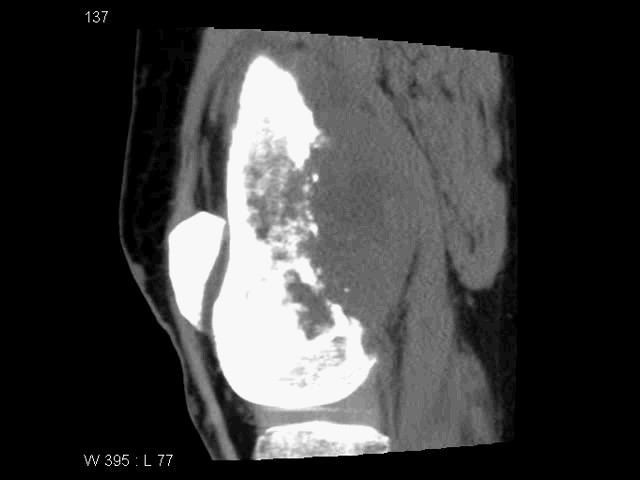

SEMAR™ (Single Energy Metal Artifact Reduction) – технологія зниження артефактів від металу з одним енергетичним рівнем є новітнім доповненням до набору адаптивних діагностичних технологій.

Цей складний алгоритм дозволяє практично виключити металеві артефакти, поліпшуючи візуалізацію імплантів в кістках і прилеглих м'яких тканинах для безпомилкової і впевненої постановки діагнозу.

На відміну від двохенергетичного сканування, Вам не потрібно заздалегідь планувати дослідження, Ви завжди можете зробити реконструкцію із застосуванням технології SEMAR™ після дослідження пацієнта, при необхідності.